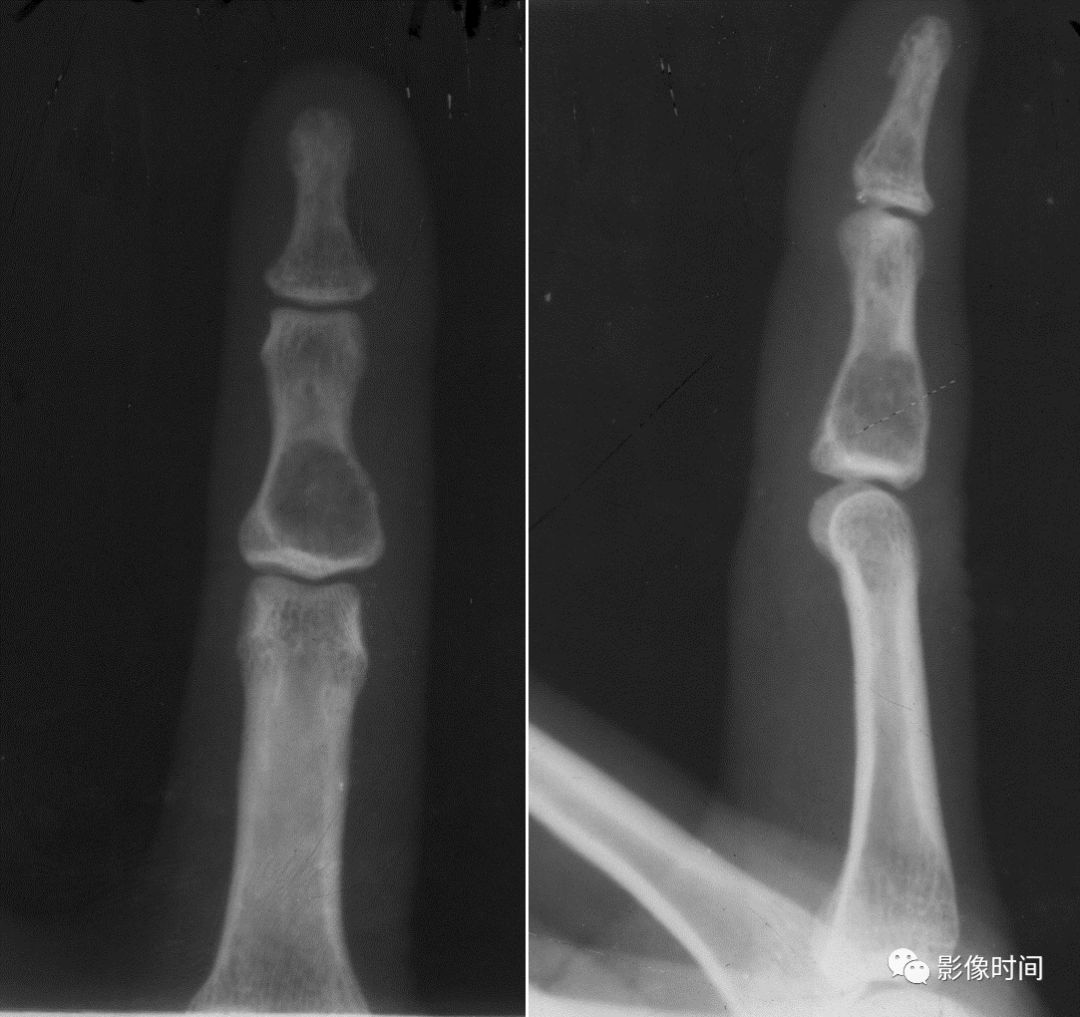

(二)膨胀性破坏  膨胀性破坏是地图样破坏的特殊形式,影像学表现为骨质破坏区骨膨胀,周围可见不同程度扩张的骨壳(图 5、图 6、图 7、图 8)。

膨胀性破坏是由于肿瘤从骨皮质内面破坏,骨外膜增生形成新生骨造成膨胀的。

引起膨胀性破坏见于大多数良性肿瘤和肿瘤样病变如单纯性骨囊肿,动脉瘤样骨囊肿、内生软骨瘤和软骨粘液纤维瘤等,少数也可见于恶性肿瘤如转移瘤、骨髓瘤等。

图 6  膨胀性破坏:骨巨细胞瘤